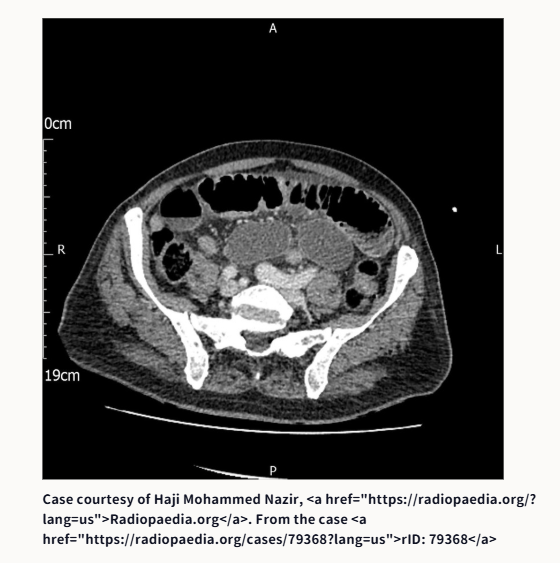

③腸閉塞です。原因は何でしょうか?

③腸閉塞の原因は、鼠径ヘルニア嵌頓です